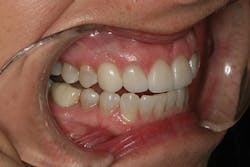

Careful technique and accurate records provided the lab with the information required to provide a result that replicated the contours of the provisional restorations. The seat appointment proceeded smoothly with no adjustments (figures 16, 17).

Conclusion

This case clearly illustrates the benefit of proper tissue management and tooth contour. Modification of tissue support and tissue training were the key elements in developing natural implant results that took this patient from being dissatisfied to loving her smile. The additional time invested in planning and manipulating soft tissues was critical to the long-term success of this implant case (figures 18, 19).